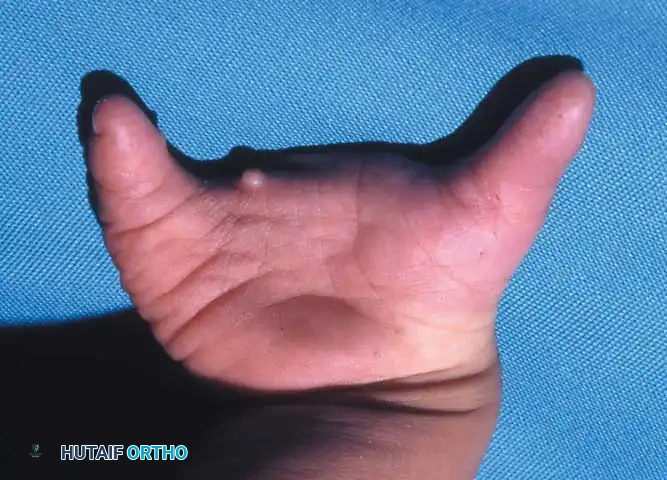

A newborn presenting with a transverse deficiency typically exhibits a slightly bulbous, well-padded stump. In more distal deficiencies, rudimentary, vestigial digital "nubbins" are frequently observed.

Fig. 76-2 Failure of formation (digital nubbins). The presence of functional wrist motion allows the limb to be used effectively as an assisting hand.

Hypoplasia of the more proximal musculature is a key clinical finding that helps differentiate true transverse deficiencies from amputations caused by congenital constriction band syndrome (amniotic band sequence). In the most common presentation—the upper forearm amputation—the forearm is usually no more than 7 cm long at birth and will reach a maximum length of approximately 10 cm by skeletal maturity.

In midcarpal amputations (the second most frequent level), the rudimentary digital remnants are almost always nonfunctional. However, because the radiocarpal joint is preserved, pronation and supination are usually possible, providing a highly functional assisting limb. Cognitive development and intelligence in these children are generally normal.